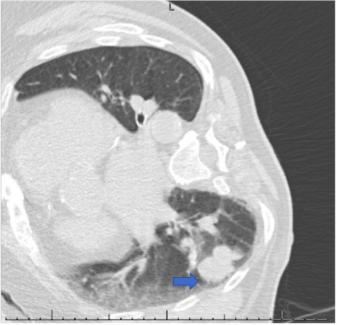

76岁男性患者,无吸烟史,有阻塞性睡眠呼吸暂停病史,接受选择性左膝全关节置换术。第二天,患者出现了非进展性连续咳嗽。胸部X线提示右肺结节状不规则阴影(图1)。胸部电脑断层扫描(CT)显示右下叶上段有一个3.2x2x4.3厘米的肿块和一个1.6厘米的颈下淋巴结(图2)。正电子发射断层扫描(PET)显示早期和延迟成像时右下叶都有活动(图3)。在身体其他部位未发现异常病灶。右下叶病变活检显示一个侵袭性,低分化,恶性黑色素瘤(图4)。患者出院后接受肺部药物治疗,两个月后接受选择性支气管镜下右下叶楔形切除术,进行淋巴结清扫和活检,并取呼吸道多处组织进行活检。最终,患者被诊断为3.7厘米的恶性黑色素瘤,边缘阴性,没有转移的迹象;因此,未发现化疗及放疗的指征。连续重复的CXR和CT扫描显示术后变化稳定,无复发迹象。到目前为止,在诊断后3年零8个月,病人继续每6个月随访一次,没有复发的记录。

图2. 胸部CT。箭头:右下叶上段3.2x2x4.3厘米的肿块。